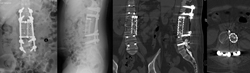

下面这个病人是个25岁的青年男性,因为下肢无力在当地医院就诊,发现T12肿瘤压迫脊髓。为了挽救神经功能,当地医生给病人做了后路椎板切除减压,椎体内肿瘤刮除及椎弓根螺钉固定手术。术后肿瘤的病理结果回报为骨巨细胞瘤。虽然神经功能改善明显,步行出院,但1年半之后肿瘤复发,不仅再次压迫脊髓而且肿瘤蔓延到相邻的3节脊椎。

图1-1,男性,25岁,术前MRI显示T12椎体、附件及椎旁肿瘤,累及椎管压迫脊髓。

图1-2,术后X片显示当地医院行后路T12附件切除减压,经椎弓根椎体肿瘤切除,T11-L1椎体间异体骨块支撑,T10,11-L1,2椎弓根螺钉固定术。

图1-3,术后1年半CT显示肿瘤复发,累及T11-L1椎体,左侧椎旁肿瘤累及腰大肌从T11蔓延到L2-3椎间盘水平。

图1-4,术后1年半MRI显示肿瘤复发,而且再次侵及椎管造成脊髓压迫。